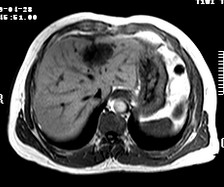

标题: CT19720:肝右叶血管瘤。肝左叶内侧段病灶考虑什么? [打印本页]

标题: CT19720:肝右叶血管瘤。肝左叶内侧段病灶考虑什么?

男,48岁,肝区不适月余,伴隐痛。

支持右叶血管瘤,左叶病灶考虑肝腺瘤。

1)不排除肝左叶肝癌。2)肝右叶血管瘤。

肝左叶炎性病变,肝癌待排。2)肝右叶血管瘤。

1.肝右叶血管瘤;2.肝左叶炎性假瘤?肝癌?建议穿刺活检.

右叶病灶典型,左叶病变慢性炎块

1、肝右叶血管瘤(典型)。

2、肝左叶病灶,强化不明显,疑炎性假瘤,建议结合临床并密切随访。

1、肝左叶炎性病变,肝癌待排。

2、肝右叶血管瘤。

肝左叶脓肿,肝癌待排。2)肝右叶血管瘤